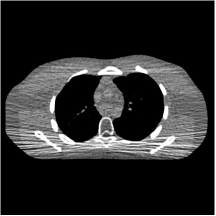

III.B.2. Simulation Framework and Visual Results

We simulate low-dose CT measurements using XCAT phantom slices with mm. The generated sinograms are of size , obtained with GE 2D LightSpeed fan-beam geometry corresponding to a monoenergetic source with incident photons per ray and no scatter. For PWLS-EP, we ran iterations of the relaxed LALM algorithm with the FBP reconstruction as initialization and regularization parameter . For the MARS model, we used the relaxed LALM algorithm for the image update step with inner iterations. We initialized PWLS-MARS schemes with the PWLS-EP reconstruction and used outer iterations for ST and all MARS schemes.

We firstly hand-tuned the reconstruction parameters () for one test slice and treated this set of parameters as the baseline. Similar to the PWLS-EP algorithm, we could determine the optimal (in terms of optimal RMSE) parameters for other testing slices by tuning the base parameters in a small range. However, we found that the change in reconstruction quality by picking a common set of parameters instead of slice-wise optimized parameters is quite small (only 0.2 HU in RMSE and without the loss of details). Therefore, the same set of parameters (baseline parameters) were used across testing cases and shown to be effective over the cases. In particular, we selected slice 48 of the XCAT phantom as the case for parameter tuning and set the regularization parameters (after tuning over ranges of values) as , , for ST, , , , , for MARS2, , , , , , , for MARS3, , , , , , , , , , , for MARS5, and , , , , , , , , , , , , , , for MARS7, respectively. In Fig. 14 in the supplement, we give the reconstructions for slice 48 of the XCAT phantom with various methods. Figs. 4 and 5 here show the reconstructions for two independent test cases (slice 20 and 60 of the XCAT phantom). Both of them used the same set of parameters obtained for slice 48. The zoom-in regions give an explicit comparison between the multi-layer sparsifying transform models and other methods such as FBP, PWLS-EP, and PWLS-ST. PWLS-MARS achieves better noise reduction and higher contrast.